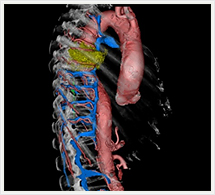

画像紹介

CTでは輪切り像の他にも立体的な画像(3D画像)を作成することもできます。そのためにはより細かくキレイな画像を撮影しなければなりません。当院では64列CTを導入しており、キレイな画像をより細かく撮影することができます。その画像を元に3D画像を作成することによって、より正確な手術のシミュレーションが可能になります。実際に手術をしたときの様子が、手術をする前に画像として見らます。外科系の手術には欠かせない技術となっておりますが、内科系でも血管内手術にも多く利用されております。

当診療放射線技術科では毎日各診療科に対して、その手術に最適な3D画像を提供しております。

以下にその3D画像を一部分紹介します。

胸部大動脈

胸部大動脈(赤)、奇静脈(青)、脊椎結核(黄)